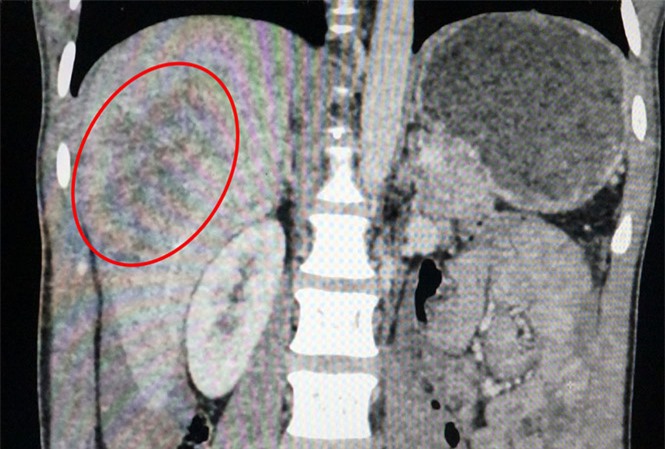

Đang nằm trong phòng chờ khoa Sinh, thai phụ đột ngột vật vã, đổ mồ hôi, da xanh nhợt. Sau chẩn đoán thai phụ bị vỡ gan, các bác sĩ đã phối hợp liên viện cứu sống cả hai mẹ con.

Trong lúc đang bơm bánh xe tải thì bất ngờ bánh xe bị nổ, luồng hơi đập vào hông phải của anh T. khiến gan của anh bị vỡ nhiều đường phức tạp.

(DNVN) - Một nam sinh lớp 7 đã bị vỡ gan xe đạp bất ngờ gãy cổ và đâm trúng vào vùng bụng khi em phóng xe với tốc độ nhanh.